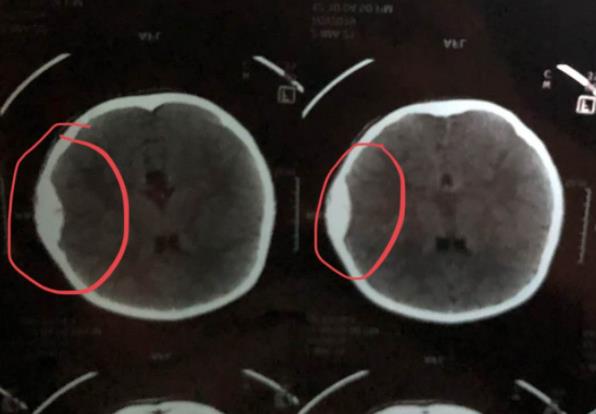

據邢女士介紹,當晚上11點多的時候,小女孩跟媽媽說有點頭疼。因為爸爸不在家,邢女士便想著第二天早上再帶孩子去做檢查。第二天一大早,邢女士就趕緊帶孩子來到了河南省婦幼保健院,大夫拍了個CT就告訴邢女士,孩子頭皮血腫,腦部有損傷,淤血面積大,位置也非常危險,需要馬上住院。于是邢女士就請了假在醫院專心陪護孩子,孩子目前精神狀態良好,但是不能下床走路,連上廁所都要抱著。

7月4日,醫院給孩子補查了一個片子,診斷證明為右側硬膜外血腫,右側頂骨折,頭皮血腫。當天,邢女士家人和世嘉游泳健身公園茂店取得了聯系,并告知了孩子的具體情況,該店一位李姓經理當即表示會全力配合孩子的治療,該承擔的責任絕不推諉。7月7日,邢女士家人再次與李經理微信聯系未得到回復。7月8日,撥打李經理電話無人接聽。一邊是受傷的孩子,一邊是無暇顧及的工作,心急如焚的李女士就投訴到了東方今報的微信后臺。